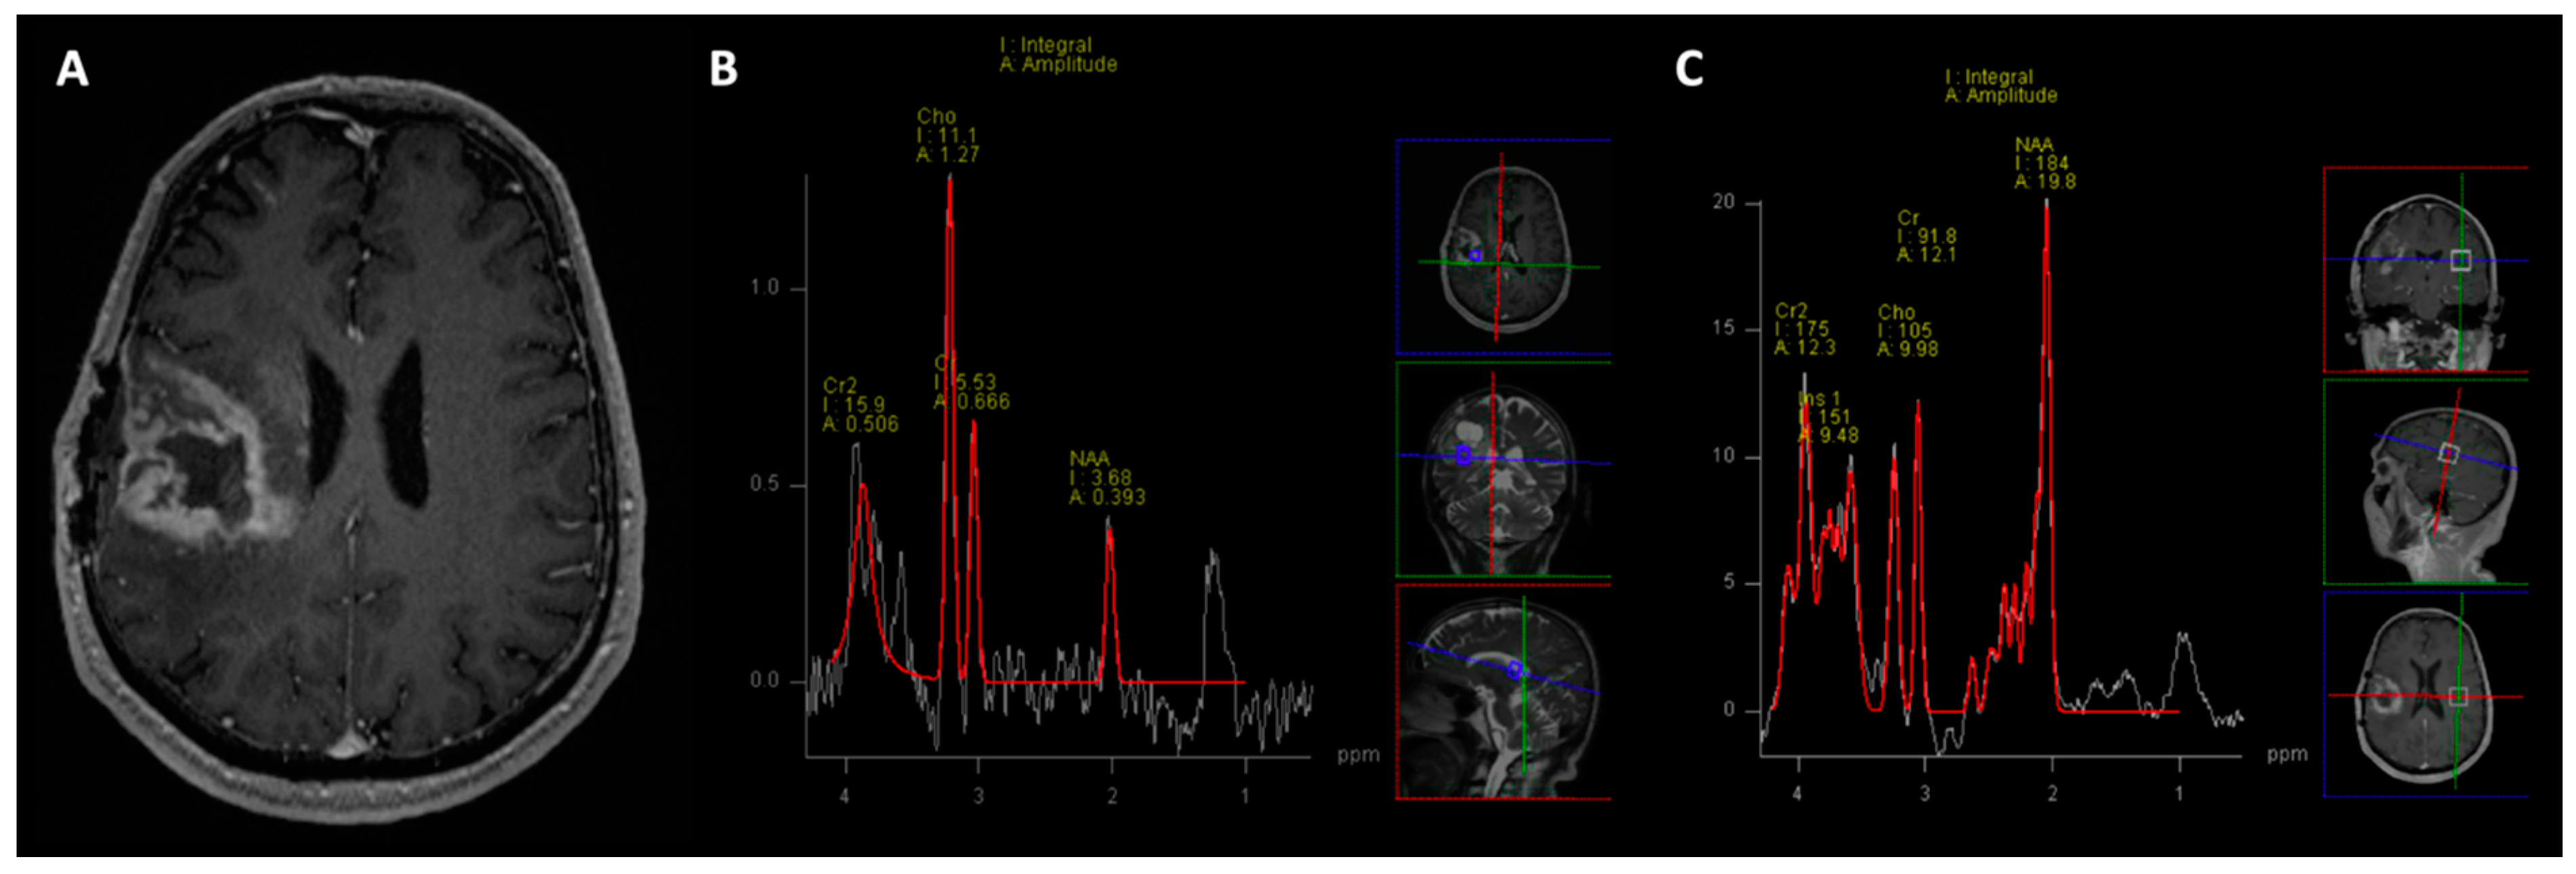

- Kazda, T.; Bulik, M.; Pospisil, P.; Lakomy, R.; Smrcka, M.; Slampa, P.; Jancalek, R. Advanced MRI increases the diagnostic accuracy of recurrent glioblastoma: Single institution thresholds and validation of MR spectroscopy and diffusion weighted MR imaging. Neuroimage Clin. 2016, 11, 316–321. [Google Scholar] [CrossRef]

- Galijasevic, M.; Steiger, R.; Mangesius, S.; Mangesius, J.; Kerschbaumer, J.; Freyschlag, C.F.; Gruber, N.; Janjic, T.; Gizewski, E.R.; Grams, A.E. Magnetic Resonance Spectroscopy in Diagnosis and Follow-Up of Gliomas: State-of-the-Art. Cancers 2022, 14, 3197. [Google Scholar] [CrossRef]

- Aseel, A.; McCarthy, P.; Mohammed, A. Brain magnetic resonance spectroscopy to differentiate recurrent neoplasm from radiation necrosis: A systematic review and meta-analysis. J. Neuroimaging 2023, 33, 189–201. [Google Scholar] [CrossRef]

| Disease | Myoinositol | Creatine | Choline | NAA | Lipid-Lactate | Chol/Cr | Chol/NAA |

|---|---|---|---|---|---|---|---|

| GBM | ↓ | ↓ | ↑ | ↓ | ↑ ↑ | >2.5 | >2.2 |

| CVA | ↓ | ↓ | ↑ (Lactate) | ||||

| TMS | - | ↓ | ↑ | ↓ | ↑ (Lactate) | ↑ | ↑ |

| Oligodendroglioma | ↑ | ↓ | ↑ | ↓ | ↑↑ | ↑ | ↑ |

| Metastasis | - | - | ↑ | ↓ | ↑ | ↑ > 1.24 | ↑ > 1.11 |